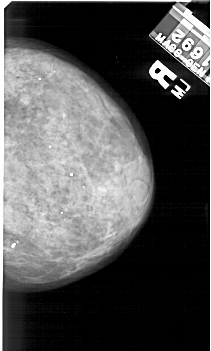

A_1420_1.RIGHT_CC

RIGHT_CC LINES 4906 PIXELS_PER_LINE 2941 BITS_PER_PIXEL 12 RESOLUTION 43.5 NON_OVERLAY

RIGHT_MLO LINES 5206 PIXELS_PER_LINE 3061 BITS_PER_PIXEL 12 RESOLUTION 43.5 NON_OVERLAY